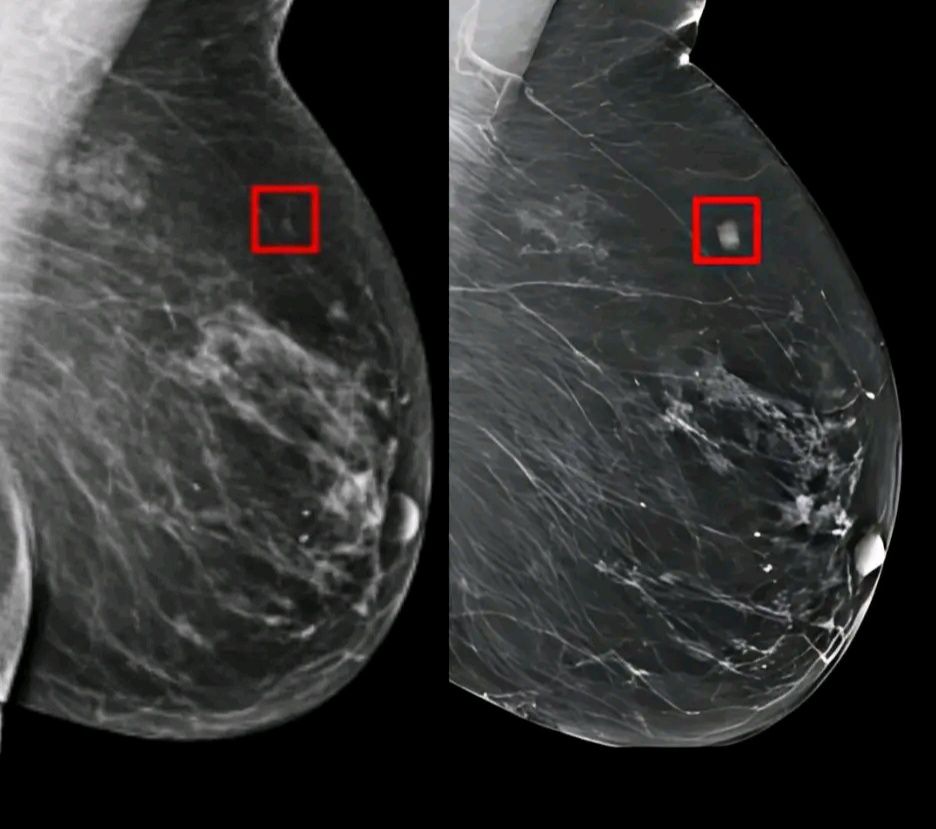

Το σύστημα τεχνητής νοημοσύνης, με την ονομασία AsymMirai, έχει σχεδιαστεί για να αναλύει τις μαστογραφίες με έναν τρόπο που ξεφεύγει από τα παραδοσιακά πρότυπα. Αντί να αναζητά όγκους ή ανωμαλίες που ήδη υπάρχουν, επικεντρώνεται σε κάτι πιο διακριτικό: στις ασυμμετρίες ανάμεσα στο δεξί και το αριστερό στήθος.

Αυτές οι μικρές διαφορές, που πολλές φορές περνούν απαρατήρητες από το ανθρώπινο μάτι, κρύβουν πολύτιμες ενδείξεις για μελλοντικό κίνδυνο. Το AI εντοπίζει και «διαβάζει» αυτές τις αποκλίσεις, δημιουργώντας ένα προγνωστικό προφίλ που δείχνει ποια γυναίκα έχει αυξημένες πιθανότητες να εμφανίσει καρκίνο τα επόμενα χρόνια.